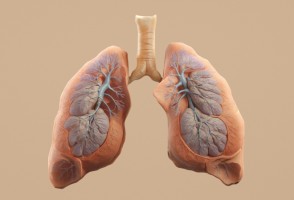

Obesidad e inflamación pueden acelerar el envejecimiento de los pulmones y aumentar el riesgo de EPOC

Un estudio con casi 900 adultos indica que, aunque el tabaquismo sigue siendo el principal factor de riesgo para la pérdida de la función pulmonar, la inflamación sistémica y la obesidad también aumentan el riesgo de desarrollar enfermedad pulmonar obstructiva crónica